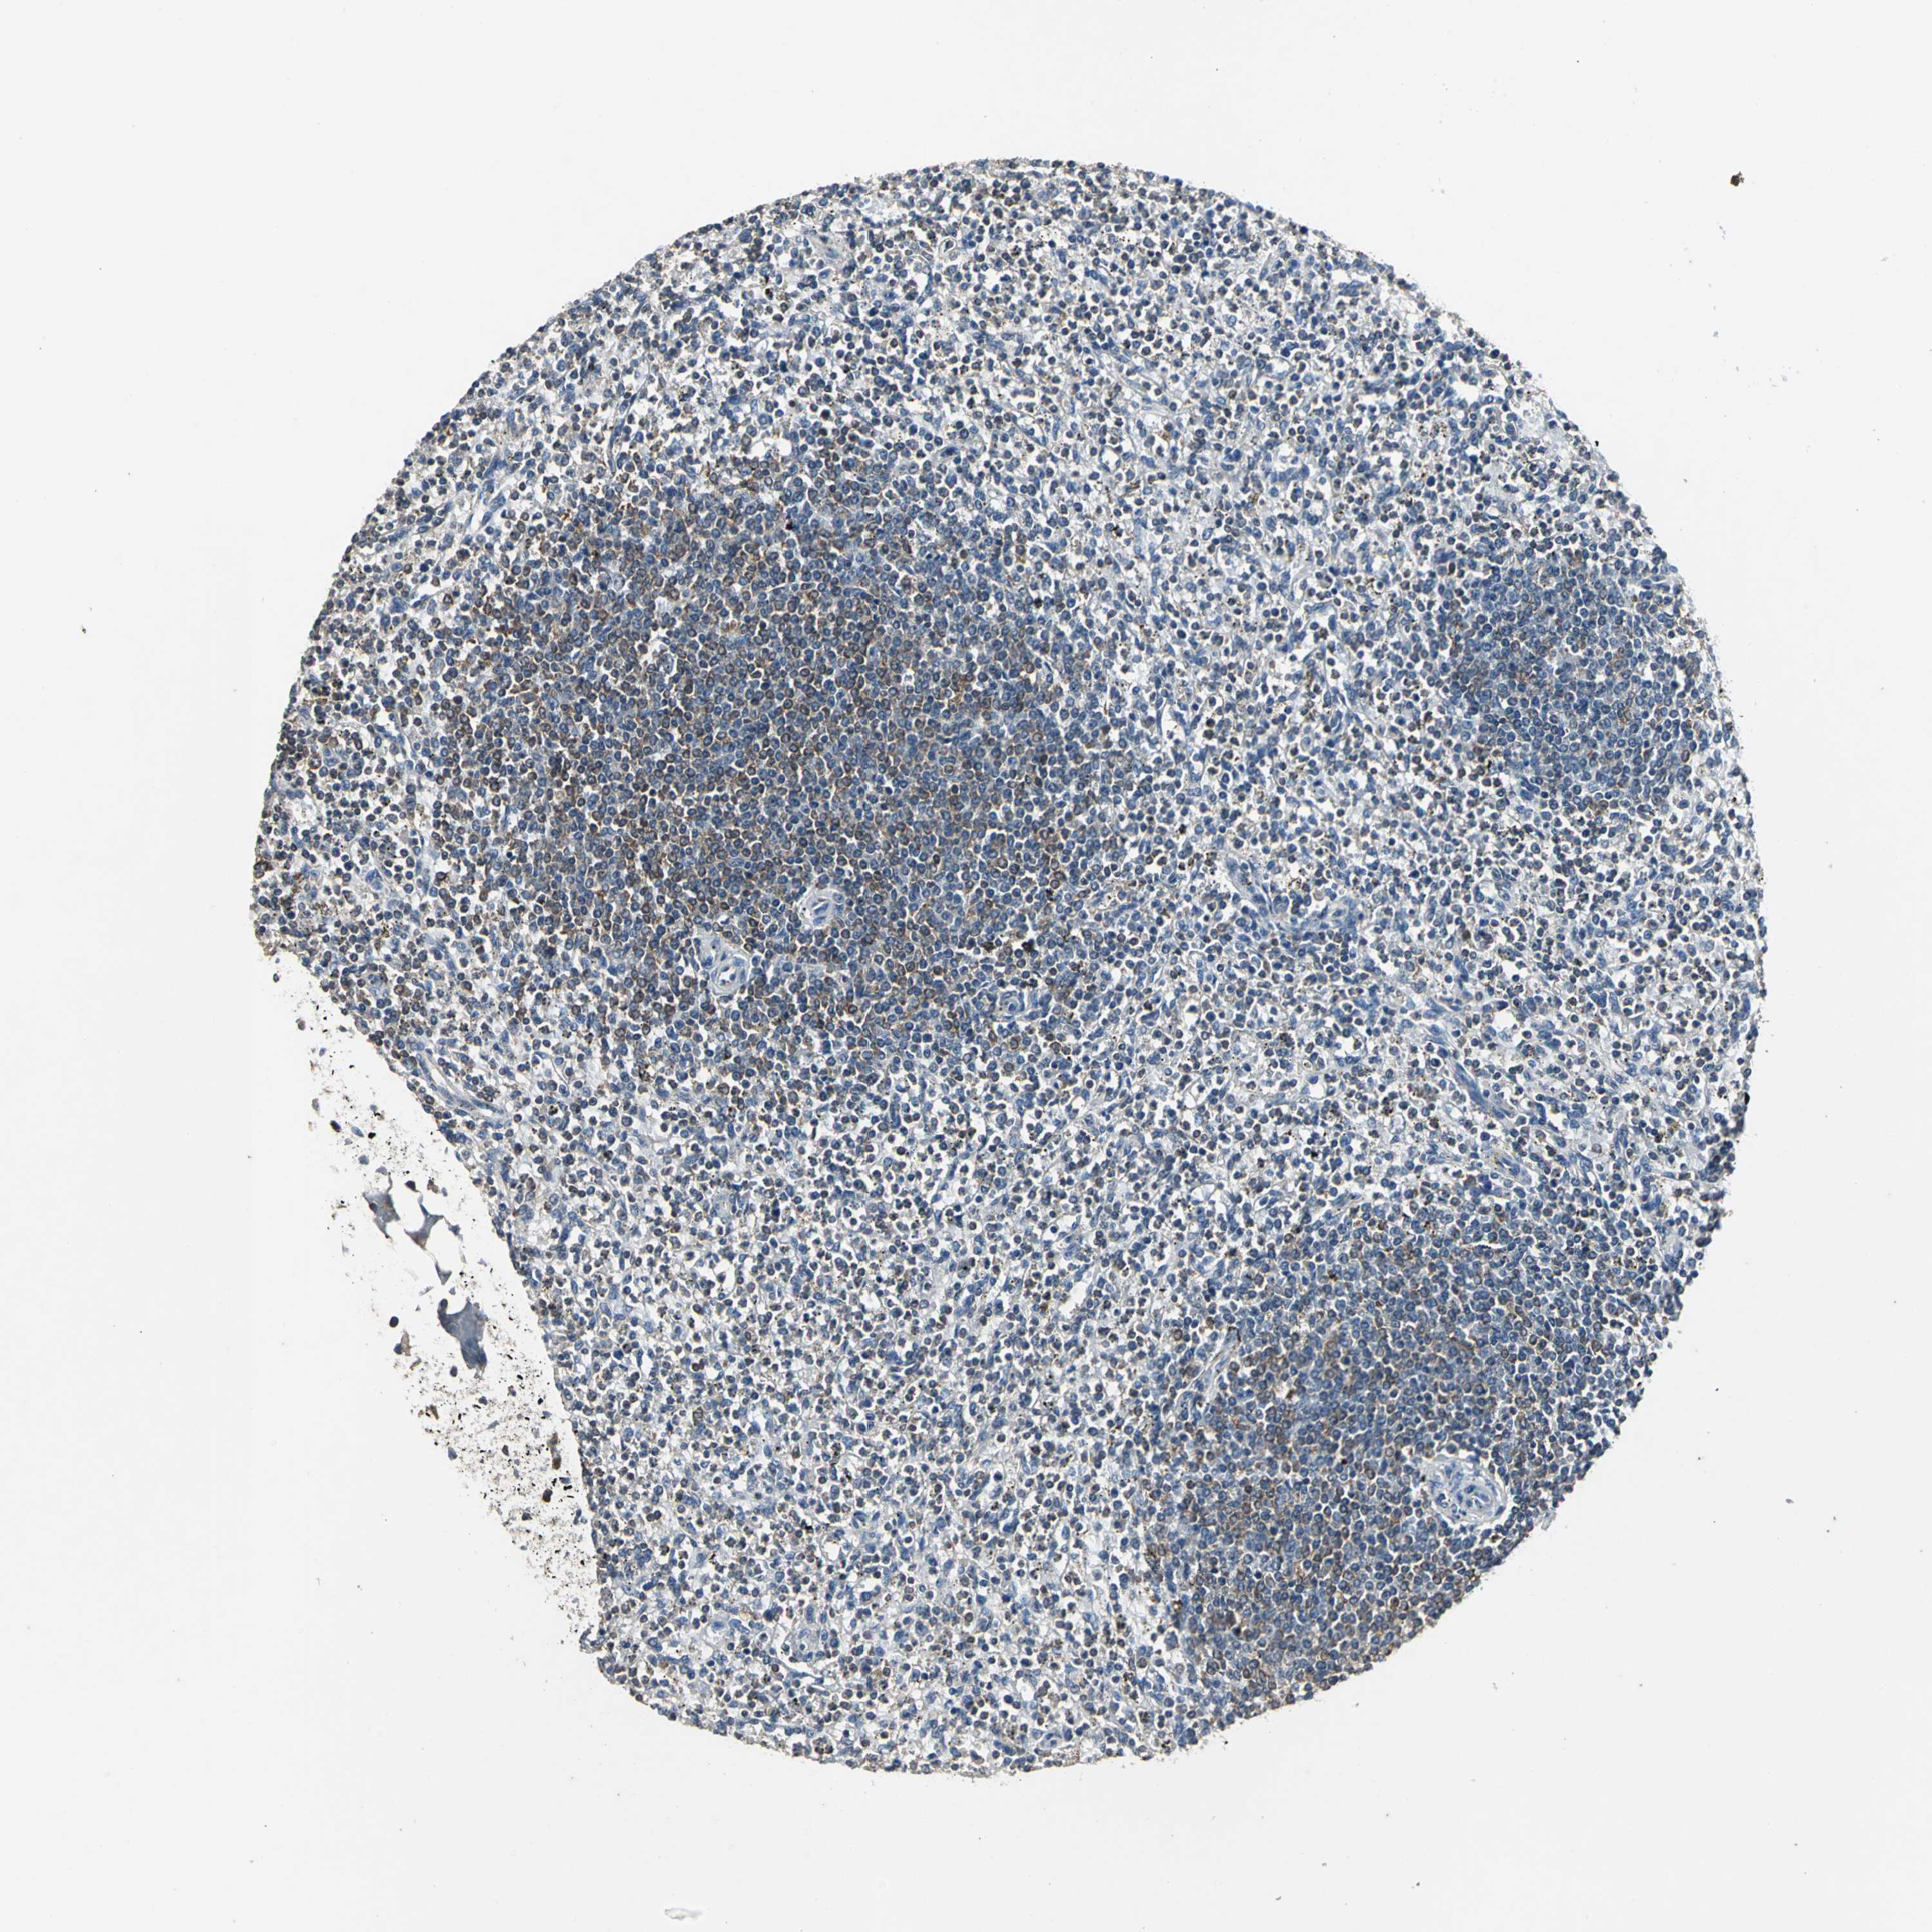

SPLEEN - Antibody stainingi

Antibody staining in the annotated cell types in the current human tissue is reported as not detected, low, medium, or high, based on conventional immunohistochemistry profiling in selected tissues. This score is based on the combination of the staining intensity and fraction of stained cells.

Each image is clickable and will lead to virtual microscopy that enables deeper exploration of all samples and also displays staining intensity scores, fraction scores and subcellular localization as well as patient and tissue information for each sample.

Antibody HPA004895Antibody CAB013018

Cells in red pulp MediumLow

Cells in white pulp MediumMedium